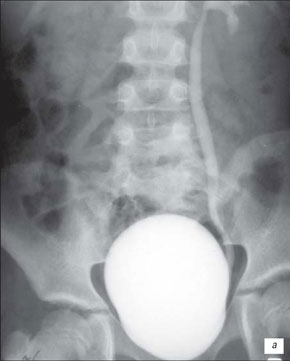

Висхідна цистографія

На даній рентгенограмі спостерігаємо активно-пасивний міхурово-сечовий рефлюкс зліва 4 ступені. Виражена дилатація чашечко-мисочкової системи, деформація чашок.

а – у фазі максимального наповнення сечового міхура, пасивний рефлекс;б – у фазі сечовипускання, активний рефлекс.